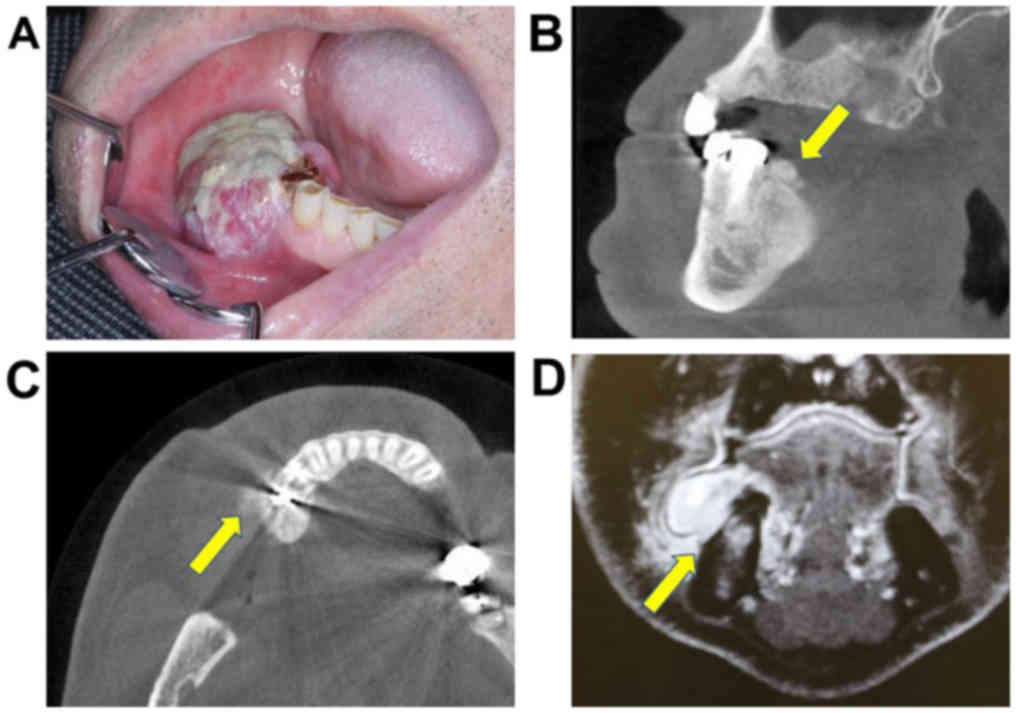

Physical examination showed an elastic-hard,

3.5×2.0-cm mass of the right mandibular premolar gum (Fig. 2A). No lymphadenopathy was found in the

neck region. Panorama X-ray and subsequent contrast-enhanced CT

scans from the head to chest and contrast-enhanced magnetic

resonance imaging (MRI) of the head and neck were performed. A

3.5×3.0×2.5-cm mass without bone resorption or infiltration was

observed. CT scan showed new bone formation on the mandible surface

(Fig. 2B and C). Contrast-enhanced

fat-suppression T1-weighted MRI showed a high-signal mass around

the mandible bone; however, no invasion to the bone was found

(Fig. 2D). The signal of the bone

marrow was considered as a slight bone marrow edema. No other

lesion was detected in the neck, bones, or lungs by the above